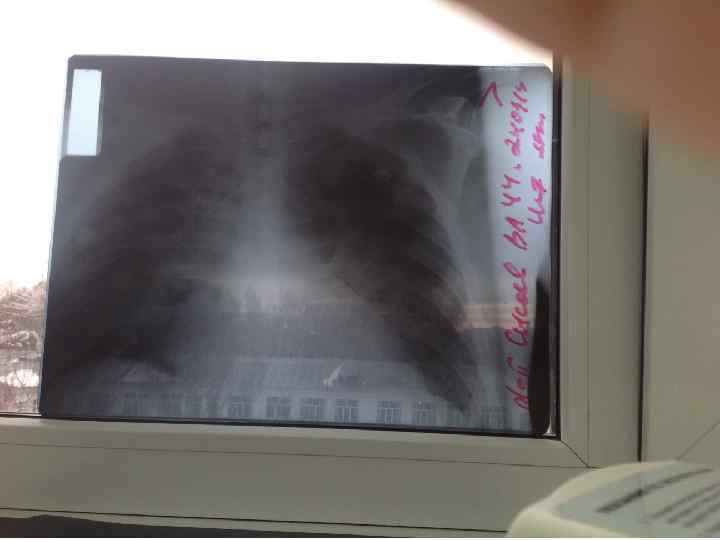

Разберемся? Редкий случай TRALI на гемотрансфузию n n n Дано: Мужчина, 44 года. Ds: C-r pancreas. Многократное оперативное лечение с формированием анастомозов ЖКК Гемотрансфузия в объеме 1200 Эр массы + 750 СЗП